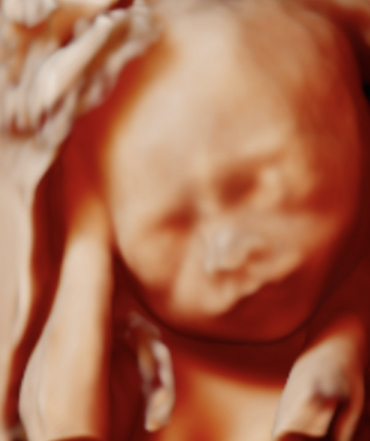

Pečujeme o nekomplikovaná i velmi riziková těhotenství

Specializujeme se na:

screening a diagnostiku genetických vad budoucího miminka , screening a diagnostiku vrozených orgánových vad budoucího miminka vyšetření vícečetných těhotenství , zvláště jednovaječných diagnostiku, sledování a řešení poruch růstu budoucího miminka screening, prevenci a sledování mateřských komplikací v těhotenství (preeklampsie, cukrovka, vysoký krevní tlak a další)